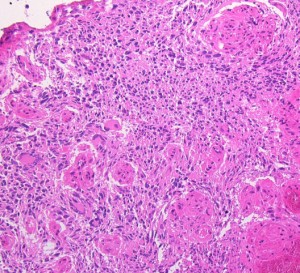

下の病理写真は,ある患者さんから私に送られたものです。20代で前頭葉の膠芽腫になってから21年経って生存しておられるということです。2度の開頭術と放射線治療と化学療法(複数回)を受けておられます。患者さんに病理診断が間違っているのではないかと返事をしたら,下にある画像を送ってくださいました。病理診断は,一見したところは多形膠芽腫 グリブラに間違いありませんでした。でも,ーーー

(下の画像は患者さんの許可を得て掲載させていただきました)

bizarre! 異様な細胞が混在しています。核多型が目立ち,多核巨細胞も混じる典型的な膠芽腫の像です。下の左の画像は血管内皮の肥厚 endovascular proliferationがあり,下の右のKi-67染色では核濃染像が多く核分裂能が高いことを示します。しかし,——

左のGFAP染色では一部の細胞が染色されません,右のHE染色では豊富な血管増殖の間に空砲 perinuclear halo を有した細胞増殖が見られます。さらに,–

腫瘍の部分像として明らかに乏突起膠腫が混在しています。また,どの部分をみても壊死 necrosisがありませんでした。

従って,当時の診断では,この腫瘍の形態病理診断は,退形成性乏突起星細胞腫 anaplastic oligoastrocytoma WHO grade III となります。2018年時点では,もしiDH変異があったと仮定すると,secondary glioblastoma (IDH-mutated glioblastoma)とされるかもしれません。